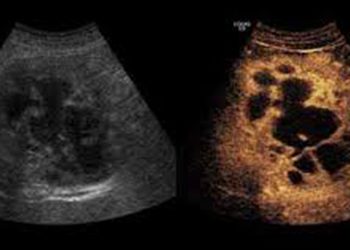

CEUS

During Contrast Enhanced Ultrasound examinations the patient is injected with microbubbles. Specialized medical software visualizes the flow of the microbubbles through all vessels and organs. CEUS is useful in oncology and infection cases.